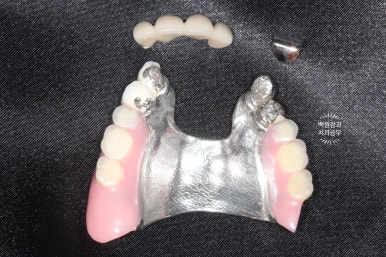

왼쪽: 위 앞니 보철물 + 부분틀니, 오른쪽: 임플란트 오버덴쳐???

사용하시던 틀니를 보아하니...

위턱에 사용하시던 보철물은 다 부러져 있었고,

아래턱에 사용하시던 틀니는 오버덴쳐인 줄 알았더니 오버덴쳐가 아니었어요.

틀니에 구멍 보이시나요?? 그냥 적당한 자리에 임플란트 두개 심고

틀니에 구멍을 내서 껴놓으셨더라구요.........

이런건 절대 교과서적인 치료가 아닙니다.

얼마나 환자분이 힘드셨을까요? ㅠㅠ

이번에 새로 제작된 틀니입니다.

왼쪽이 위턱 오른쪽이 아래턱.. 잘 모르시겠죠?

왼쪽이 위턱, 오른쪽이 아래턱입니다.

눈치 빠르신 분은 아셨을텐데요, 아래턱 틀니의 치아가 없는 조직면을 보시면 구멍이 두개 뚫려있어요.

그 부분이 나중에 입 안에 튀어나와있는 금색 부분과 연결될 자리 !!

아래턱 틀니 안쪽면에 이렇게 까만색의 파트를 연결해주면,

입안에 틀니를 장착하실 때 딸깍딸깍 뺐다꼈다를 하실 수 있게 되어요.!!

이 녀석의 이름이 바로 오버덴쳐(overdenture)입니다. :)